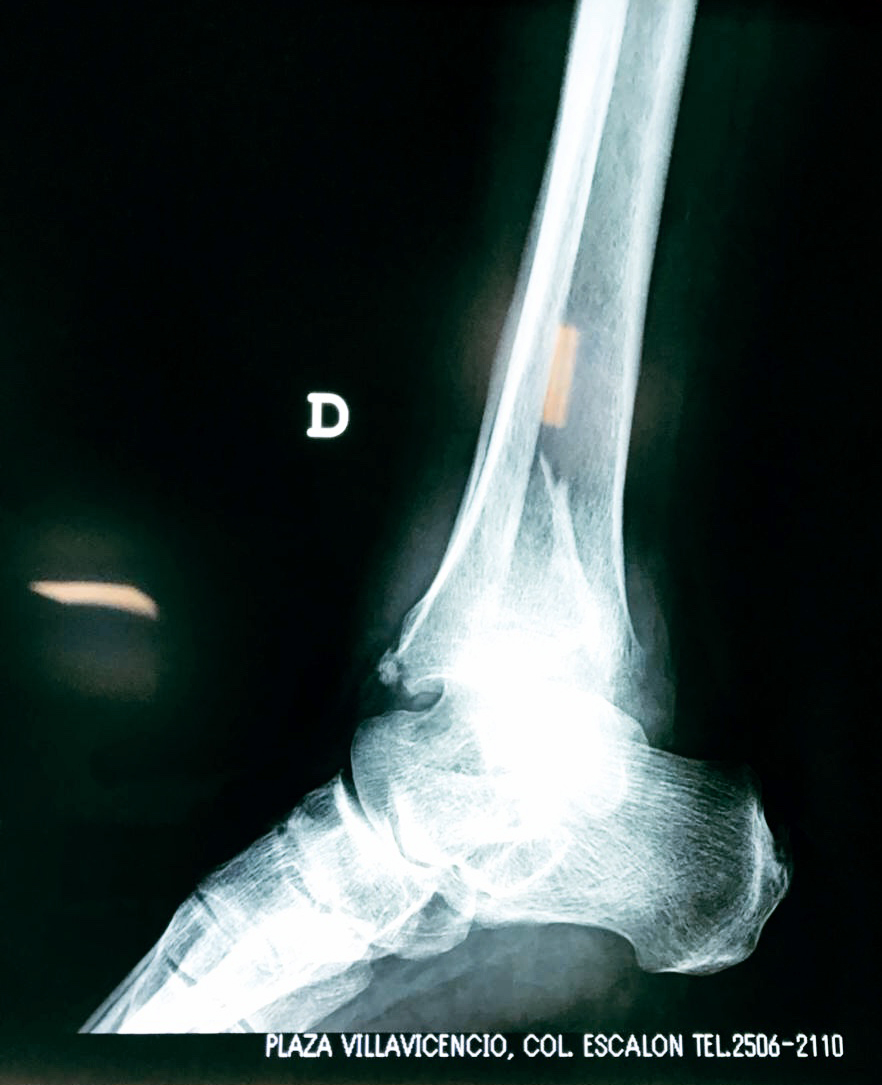

Una fractura de tobillo es la rotura de uno o más de los huesos del tobillo. Estas fracturas pueden ser:

Algunas fracturas de tobillo pueden requerir cirugía si:

- Los extremos de los huesos están desalineados entre sí (desplazados).

- La fractura se extiende hasta la articulación del tobillo (fractura intra-articular).

- Los tendones o ligamentos (tejidos que sujetan los músculos y los huesos entre sí) están rotos.

- El médico cree que sus huesos probablemente no sanen apropiadamente sin cirugía.

- El médico considera que la cirugía puede permitirle una recuperación más rápida y confiable.